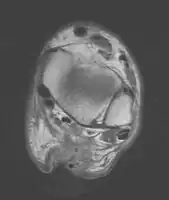

Imaging

Musculoskeletal ultrasonography can be used to determine the tendon thickness, character, and presence of a tear. It works by sending extremely high frequencies of sound through the body. Some of these sounds are reflected back off the spaces between interstitial fluid and soft tissue or bone. These reflected images can be analyzed and computed into an image. These images are captured in real time and can be very helpful in detecting movement of the tendon and visualising possible injuries or tears. This device makes it very easy to spot structural damages to soft tissues, and consistent method of detecting this type of injury. This imaging modality is inexpensive, involves no ionizing radiation and, in the hands of skilled ultrasonographers, may be very reliable.

MRI can be used to discern incomplete ruptures from degeneration of the Achilles tendon, and MRI can also distinguish between paratenonitis, tendinosis, and bursitis. This technique uses a strong uniform magnetic field to align millions of protons running through the body. These protons are then bombarded with radio waves that knock some of them out of alignment. When these protons return they emit their own unique radio waves that can be analysed by a computer in 3D to create sharp cross sectional image of the area of interest. MRI can provide unparalleled contrast in soft tissue for an extremely high quality photograph making it easy for technicians to spot tears and other injuries.

Transverse plane/Achilles tendon rupture